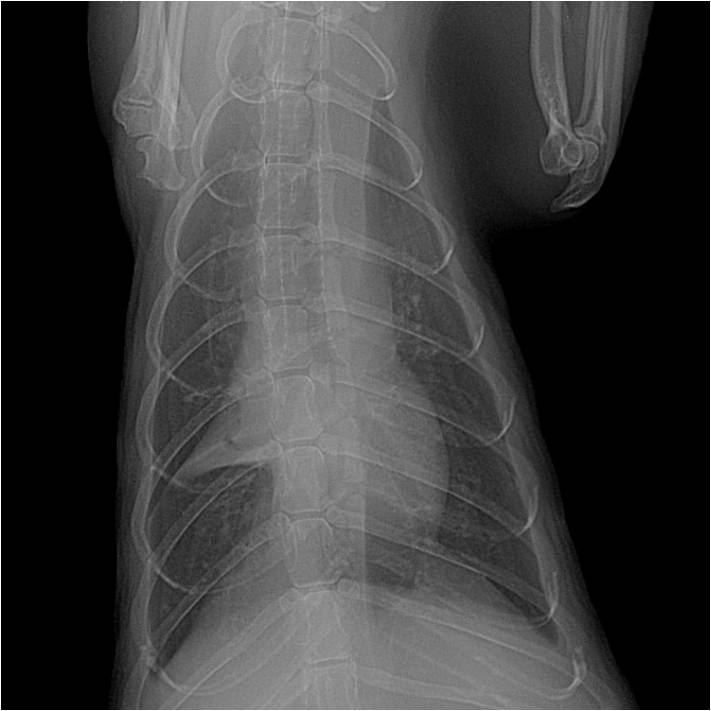

Maladie cardiaque

Les furets présentent des maladies cardiaques, en particulier lorsqu'ils sont âgés de plus de 5 ans. On recommande des visites de routine avec un examen échocardiographique afin de déceler d'éventuelle anomalie le plus précocement possible. En cas de signes cliniques, les furets sont souvent abattus et présentent des signes de détresse respiratoire. Une radiographie permettra de mettre en évidence les premiers signes de maladie cardiaque mais une échocardiographie réalisée par un vétérinaire expérimenté reste nécessaire pour confirmer le diagnostic. Le traitement fait appel à des médicaments cardiaques.